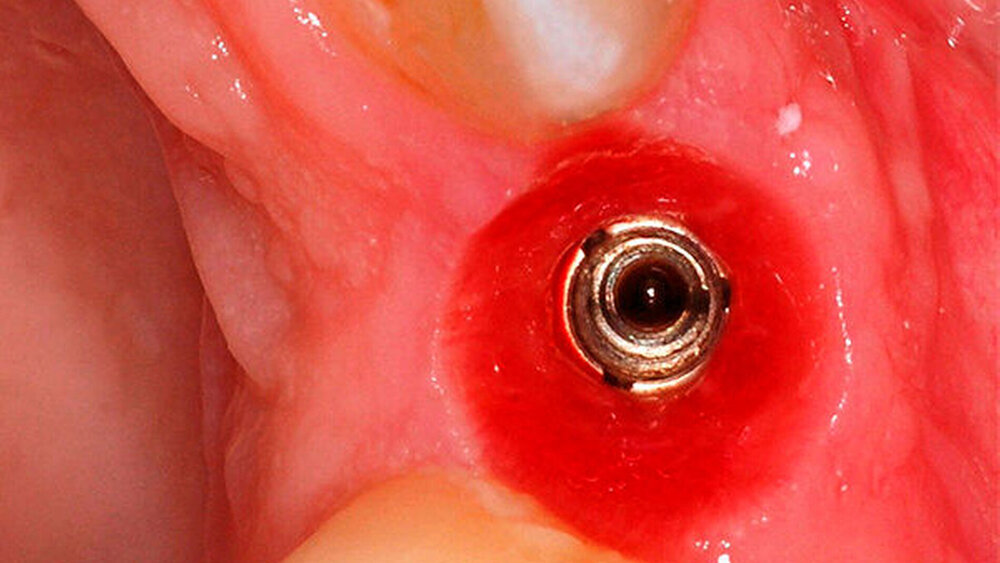

Kommen wir zur Sofortversorgung. Ziehen Sie dabei konische oder Flach-zu-flach-Verbindungen vor?

Ruppin:

Sie muss eine gute Primärstabilität ermöglichen. Die Art der Innenverbindung spielt hierbei nicht die zentrale Rolle.

Wilde:

Die neue PROGRESSIVE LINE funktioniert letztlich wie eine Spaxschraube. Sie zieht sich mit viel Kraft in den Knochen während des Eindrehens. Mit einem Implantatsystem mit einem solch aggressiven Gewinde lässt sich eine enorme Zugkraft entwickeln, die es ermöglicht, das Implantatlager zart aufzubereiten und den Knochen mit dem Implantat aufzudehnen. Das hat mit der Innenverbindung nichts zu tun. Beim Einzelfrontzahn-Implantat im Oberkiefer und einer verzögerten Sofortimplantation bei schmalem Knochen würde ich PROGRESSIVE LINE wählen, um den Knochen nach vestibulär aufzudehnen. Als CONELOG-Fan natürlich mit der konischen Verbindung. Fehlen von 3 nach 3 im Oberkiefer die Frontzähne und ich entscheide mich für die Sofortimplantation, plädiere ich für vier PROGRESSIVE-LINE-Implantate mit der CAMLOG-Verbindung, um den Knochen damit leicht zu verformen und sofort zu belasten. Gehe ich mit mehr Implantaten an den Start, funktioniert CONELOG nicht mehr als Interface. Da braucht es die Butt-Joints. Aber noch einmal: Das Tolle und wirklich Großartige ist für mich, dass das komplette Equipment gleich bleibt. Alle Hilfsteile, Healing Caps, Scanpfosten und Gingivaformer können weiterverwendet werden. Das spart uns Behandlern viel Geld.